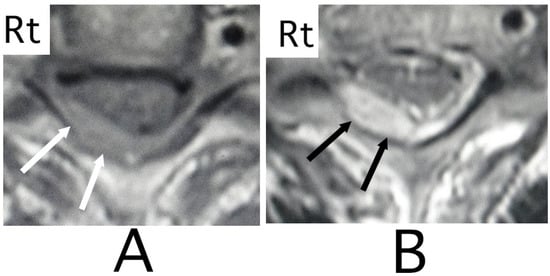

The lesion in the intracranial region or the cervical spinal cord was suspected. Computed tomography (CT) images of the head and X-ray of the cervical bone were normal; however, sagittal CT images of the cervical bone showed a slightly abnormal high-density area (HDA) behind the spinal cord at the level between C4 and C7 (Figure 3A). This abnormal HDA was located in the posterior part on the right side in axial CT images (Figure 3B). MRI analysis was performed because the presence of a hemorrhagic lesion was suspected, based on the CT findings of the cervical bone. Sagittal T1-weighted MRI showed an iso-intensity mass in the epidural space behind the spinal cord at the level from C4 to C7 (Figure 4A). The lesion was noted as a heterogeneous high-intensity mass in sagittal T1-weighted images (Figure 4B). Axial T1-weighted MRI showed an iso-intensity mass in the posterior part on the right side in the epidural space and mild compression of the spinal cord (Figure 5A). The lesion was noted as a heterogeneous high-intensity mass in axial T2-weighted images (Figure 5B).

Figure 3. CT images of the cervical bone. CT images of the sagittal position showed a slight high-density mass behind the spinal cord at the level between C4 and C7 (black arrows) (A). The mass was located diagonally posterior part on the right side (black arrows) (B). (Rt = right).